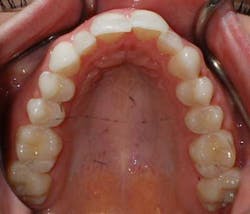

A 27-year-old female presented with a chief complaint of crowding on the upper and lower arches. Upon evaluation, it was noted that the patient had 2 mm and 4.5 mm of maxillary and mandibular arch length deficiency respectively, a missing lower left second bicuspid with primary tooth still present, small upper lateral incisors, cross-bite of the lower right canine, and lower midline shift to the right of 2 mm. (Figs. 1-8)

Figs. 1-8